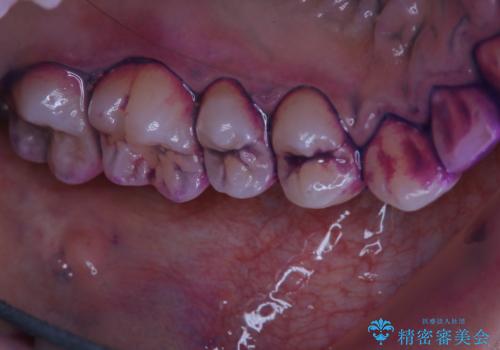

染め出し液を使ってプラークを染め出すことにより、普段の歯みがきで磨き残している場所を目で確かめることができます。

日々の歯磨きを上達するには、まずどこが磨けていないか認識することが大切です。